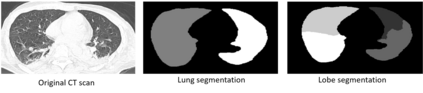

COVID-19 infection caused by SARS-CoV-2 pathogen is a catastrophic pandemic outbreak all over the world with exponential increasing of confirmed cases and, unfortunately, deaths. In this work we propose an AI-powered pipeline, based on the deep-learning paradigm, for automated COVID-19 detection and lesion categorization from CT scans. We first propose a new segmentation module aimed at identifying automatically lung parenchyma and lobes. Next, we combined such segmentation network with classification networks for COVID-19 identification and lesion categorization. We compare the obtained classification results with those obtained by three expert radiologists on a dataset consisting of 162 CT scans. Results showed a sensitivity of 90\% and a specificity of 93.5% for COVID-19 detection, outperforming those yielded by the expert radiologists, and an average lesion categorization accuracy of over 84%. Results also show that a significant role is played by prior lung and lobe segmentation that allowed us to enhance performance by over 20 percent points. The interpretation of the trained AI models, moreover, reveals that the most significant areas for supporting the decision on COVID-19 identification are consistent with the lesions clinically associated to the virus, i.e., crazy paving, consolidation and ground glass. This means that the artificial models are able to discriminate a positive patient from a negative one (both controls and patients with interstitial pneumonia tested negative to COVID) by evaluating the presence of those lesions into CT scans. Finally, the AI models are integrated into a user-friendly GUI to support AI explainability for radiologists, which is publicly available at http://perceivelab.com/covid-ai.